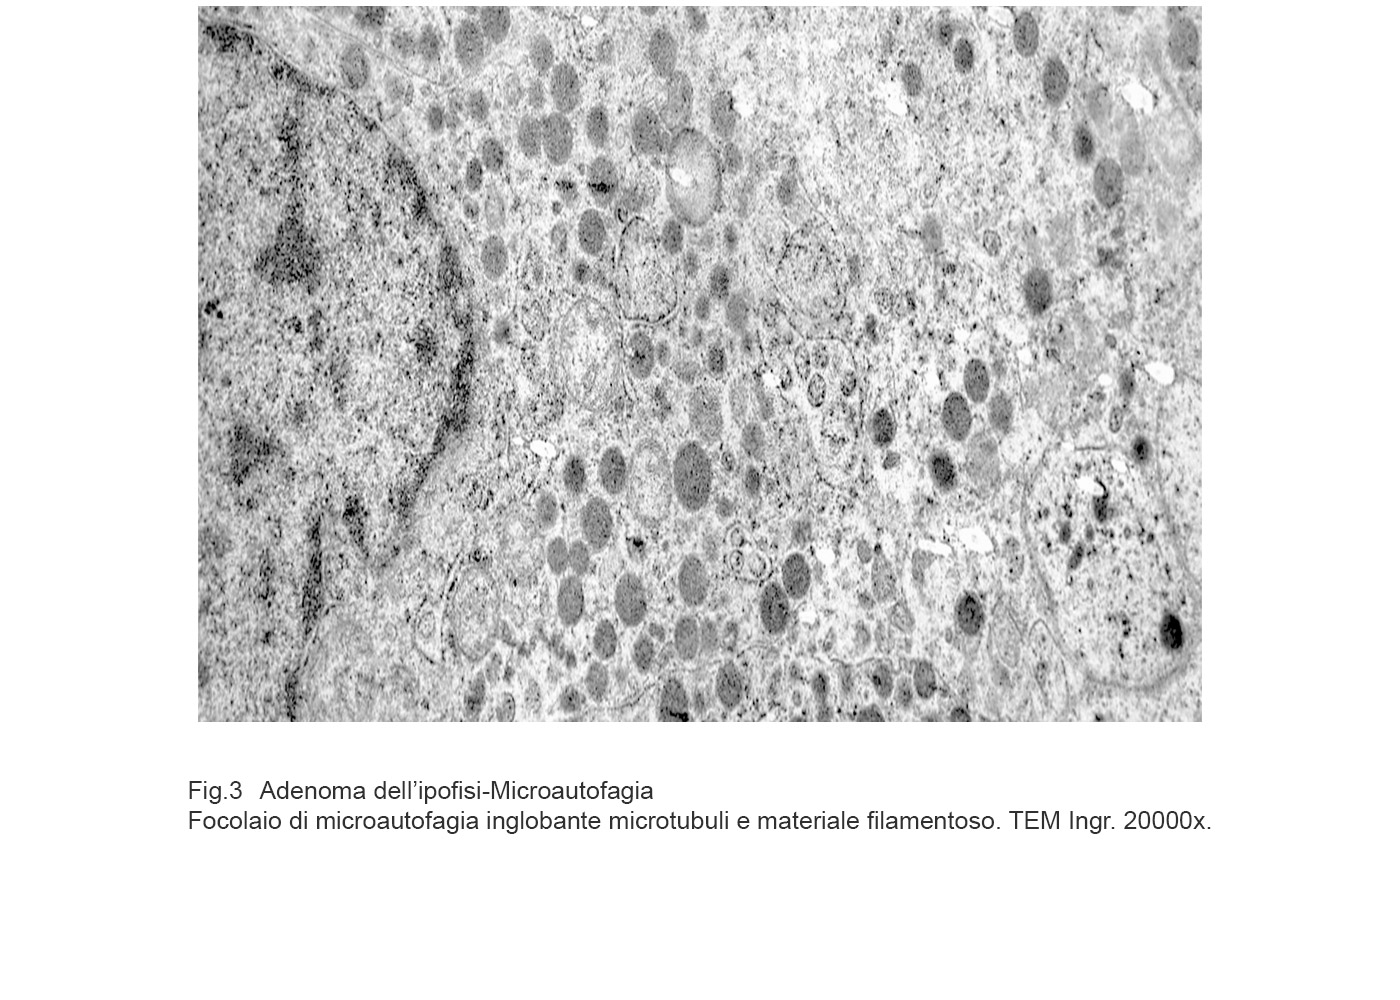

MICROAUTOFAGIA

I focolai di microautofagia si ritrovano frequentemente commisti a mitocondri disfunzionali e a reticolo- endoplasmatico in stato di stress.

Essi sono di piccole dimensioni, appaiono come vescicole, delimitate da una membrana a doppio strato, immerse nel citosol e

ricolme di materiale amorfo oppure di materiale amorfo commisto a frammenti filamentosi.

Fig.3  Fig.3a